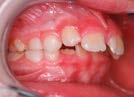

Andréa Case treated with EF Kid

Treatment time: 24 months

• Maxillary left endoalveolia • Severe dental crowding

Wearing of EF Kid for 12 months

7 y.o.

Results: Closure of open bite • Improved arch rounding

… then with EF T Slim

Wearing of EFT Slim for 12 months

Results: guiding of adult teeth